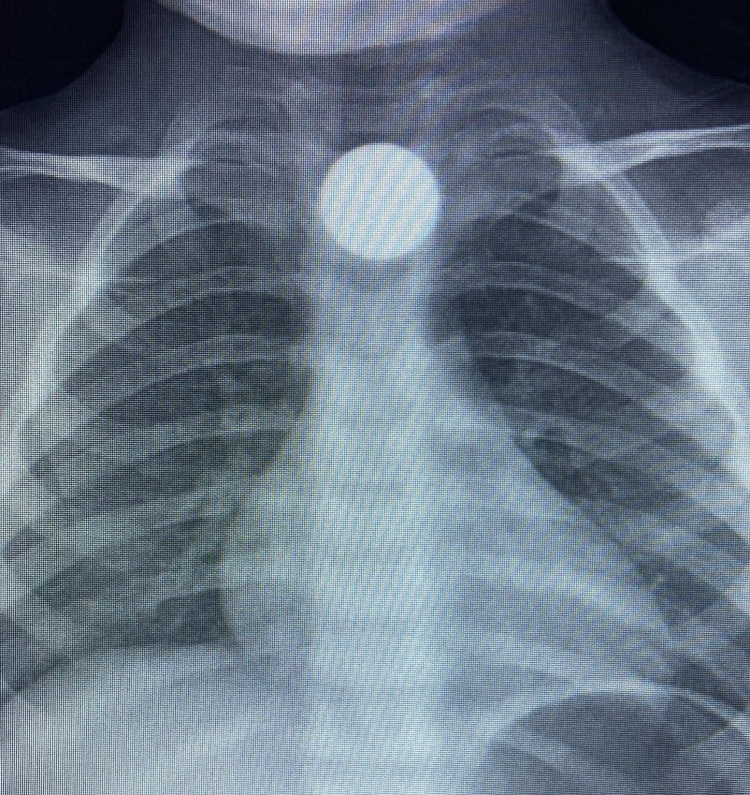

Olay, İnegöl’ün kırsal Yeniceköy Mahallesi’ndeki bir evde meydana geldi. 3 yaşındaki Bilal K., evde yerde bulduğu 50 kuruş madeni parayı ağzına atıp yuttu. Olayı fark eden ailesi tarafından çocuk özel araçla İnegöl Devlet Hastanesi’ne kaldırıldı. Yapılan tetkiklerde yemek borusunda takılı kalan madeni para görüldü. Çocuk ilk tedavinin ardından ambulansla Bursa Yüksek İhtisas Eğitim Ve Araştırma Hastanesi’ne sevk edildi.